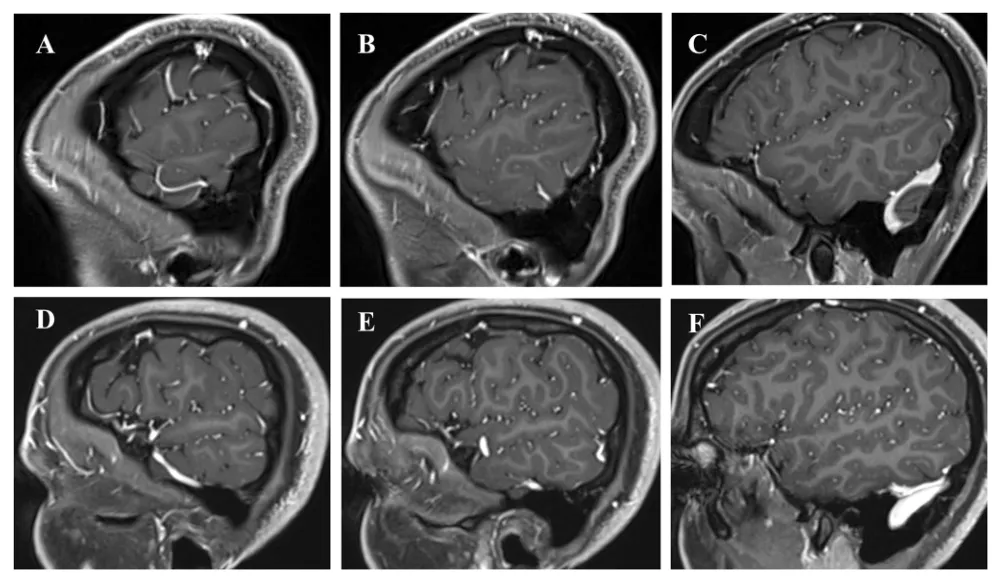

图1.左侧Labbé静脉的两种不同走行模式的矢状位T1增强MRI。从外侧裂到横窦-乙状窦交界处的曲折走行(A–C),以及沿岩骨的较长且低位的水平走行(D–F)。

对于所有类型的经岩骨入路,均需在轴位和矢状位增强MRI上仔细排查Labbé静脉及其他颞叶静脉的走行路线。临床经验表明:若Labbé静脉沿颞叶呈较长且偏低的水平走行,则开颅操作中损伤它的风险将明显增高。